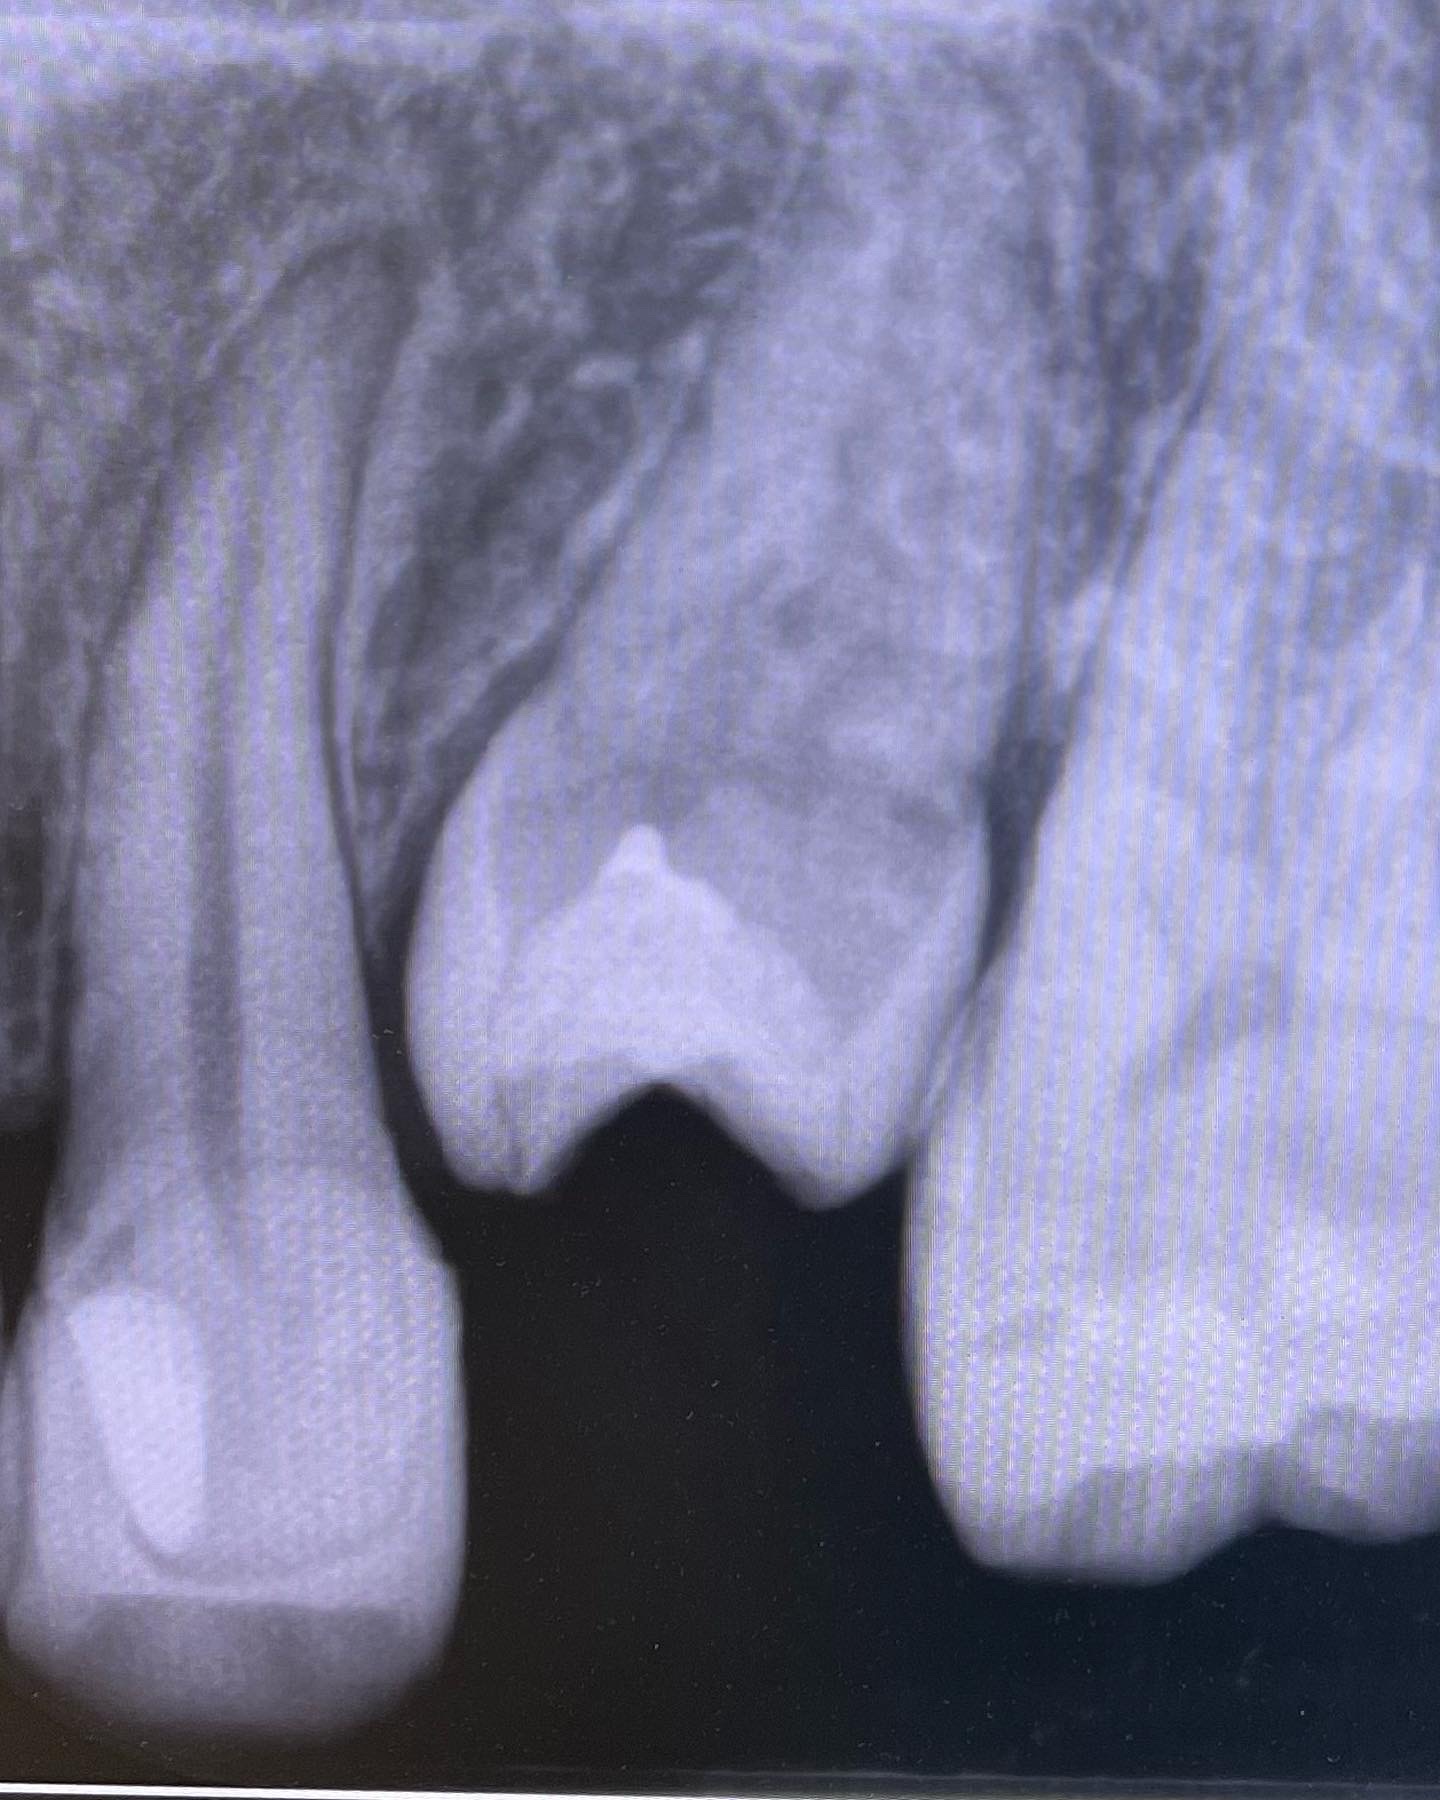

Vital Pulp Therapy→Er-YAGレーザーとMTAセメントミエール症例。

低位の歯が露髄。Er-YAGレーザーにて歯髄蒸散し、MTAとCRにて修復。痛みでませんように!失活しませんように!祈るしかありません。

生活歯のまま保存して、ワイヤー矯正までもっていきたいと切に願ってます。